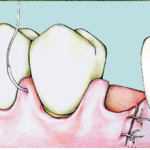

Sutura sospesa doppia

Molteplici sono le tecniche di sutura proposte e ognuna di esse è in grado di esercitare in modo peculiare una trazione sul lembo precedentemente sollevato così da poterlo posizionare e stabilizzare nella posizione desiderata.